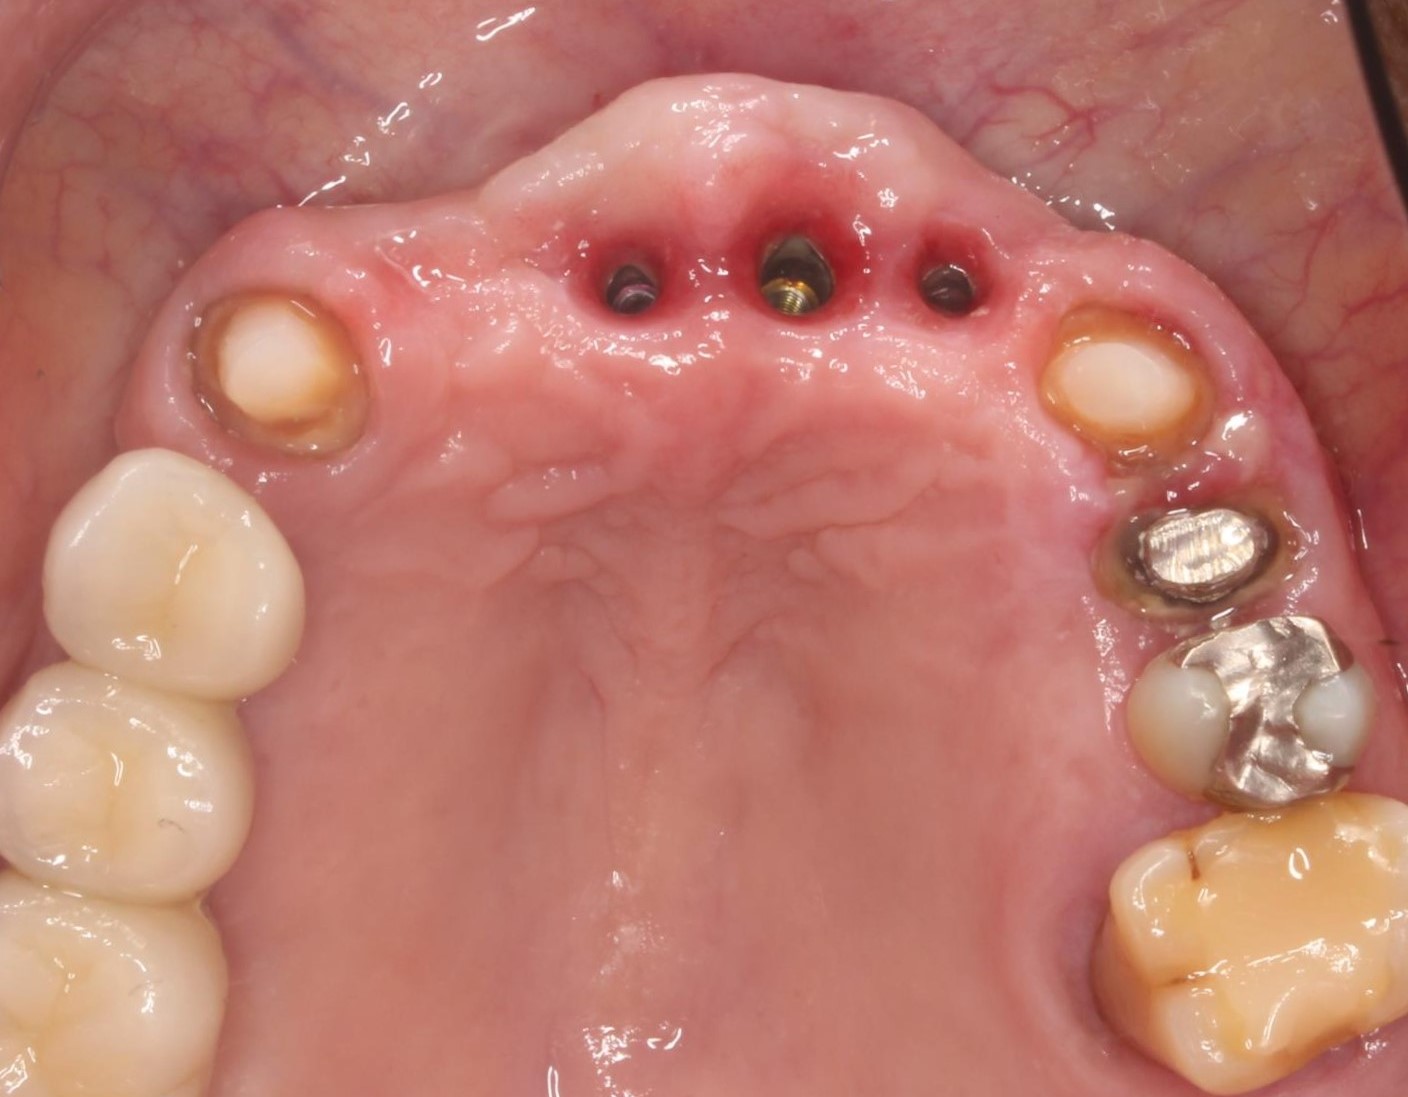

症例06

60代 男性 入れ歯の取り外しが不便

治療前

治療前

治療後

治療後

| 主訴 | 入れ歯の取り外しが面倒であり、食事の度にものがはさまる。 |

|---|---|

| 年代・性別 | 60代・男性 |

| 治療部位 | 上顎2~2 |

| 治療費用 | インプラント手術料 300,000円×3=900,000円 当日即時荷重 50,000円×4=200,000円 筋肉内鎮静法 30,000円 セラミック上部 150,000円×4=600,000円 |

| 手術回数 | 1回 |

| 治療期間 | 6ヶ月 |

| 手術時間 | 2時間 |

| 治療回数 | 6回 |